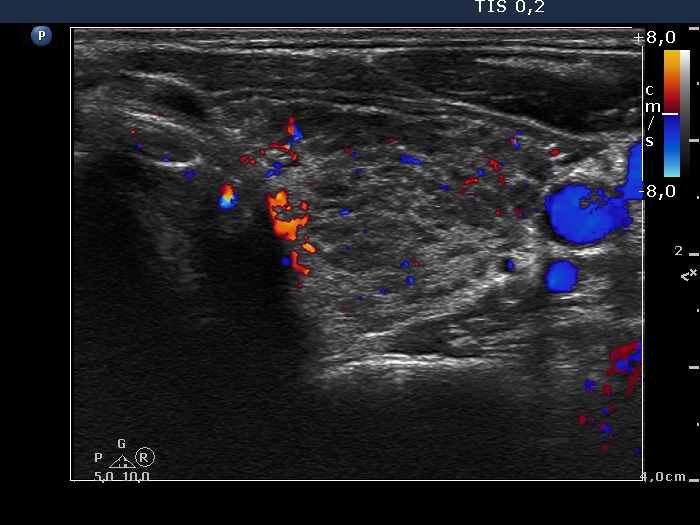

Lymphocytic thyroiditis - case 467 (ultrasonographic picture 7)

Left lobe, transverse scan, color Doppler mode. The vascularization is not specific.